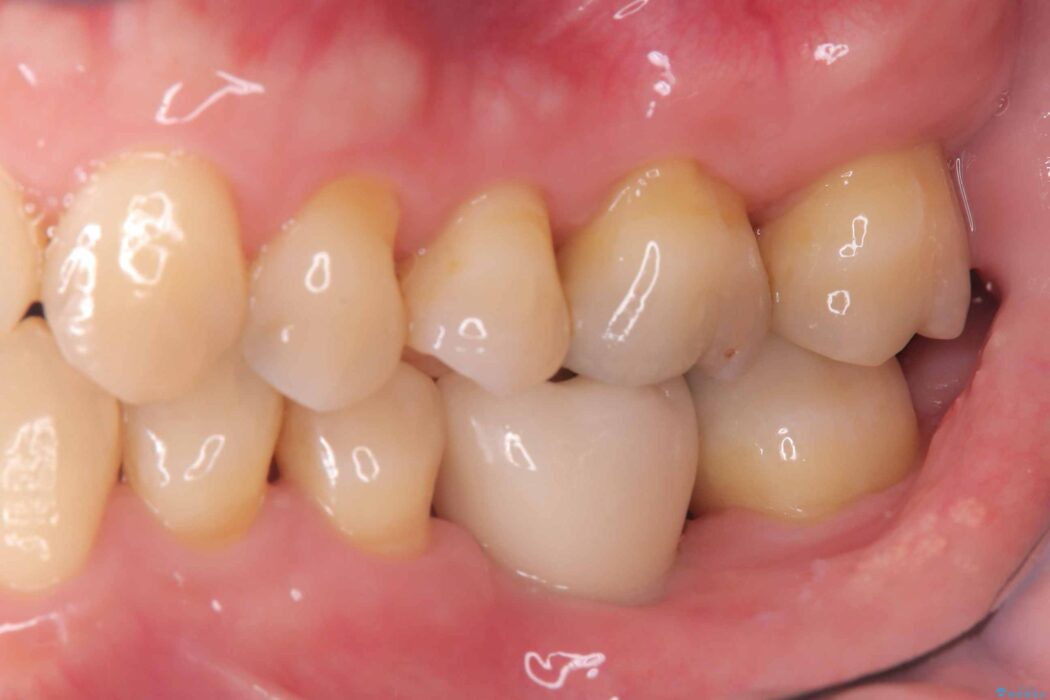

治療後について

インプラント治療は手術が一度で完了し、術後の痛みもほとんどありませんでした。

機能面・審美面ともに大きく改善され、大変ご満足いただけました。